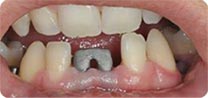

安卓健临床案例分享

安卓健种植产品销往全球100多个国家精密工程CFDA

权威认证,可放心使用。安卓健种植体手术程序简单,

更少创伤,更快恢复,更加安心。